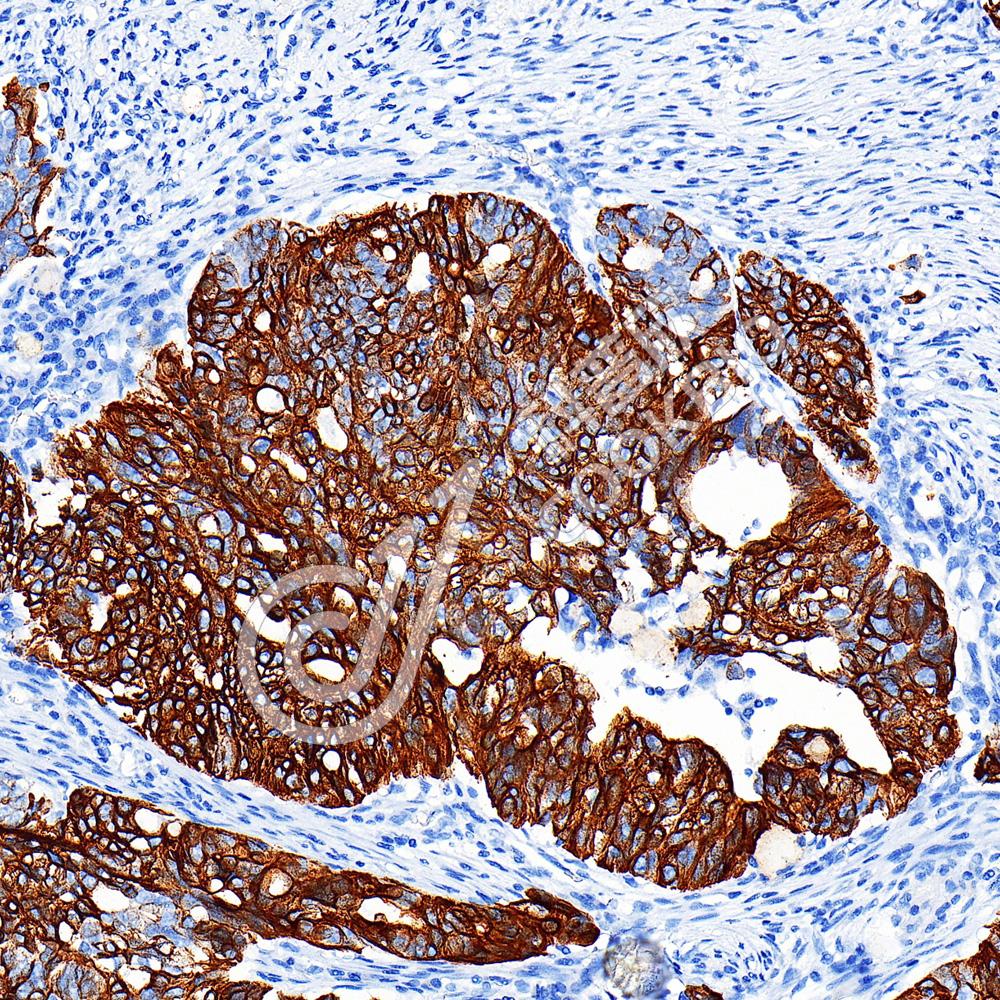

IHC检测Cytokeratin 17蛋白(货号 K5450183).

样品: 人卵巢癌, 4%多聚甲醛 (货号KSG1101) 固定12-24小时.

抗原修复: 柠檬酸抗原修复液(干粉, pH 6.0) (KSG1201), 高压锅均匀喷气计时2分钟.

—抗: 1: 2000稀释, 4℃ 孵育过夜.

二抗: S-vision免疫组化多聚二抗(山羊抗小鼠), 即用型(货号KB3903), 室温孵育20分钟.